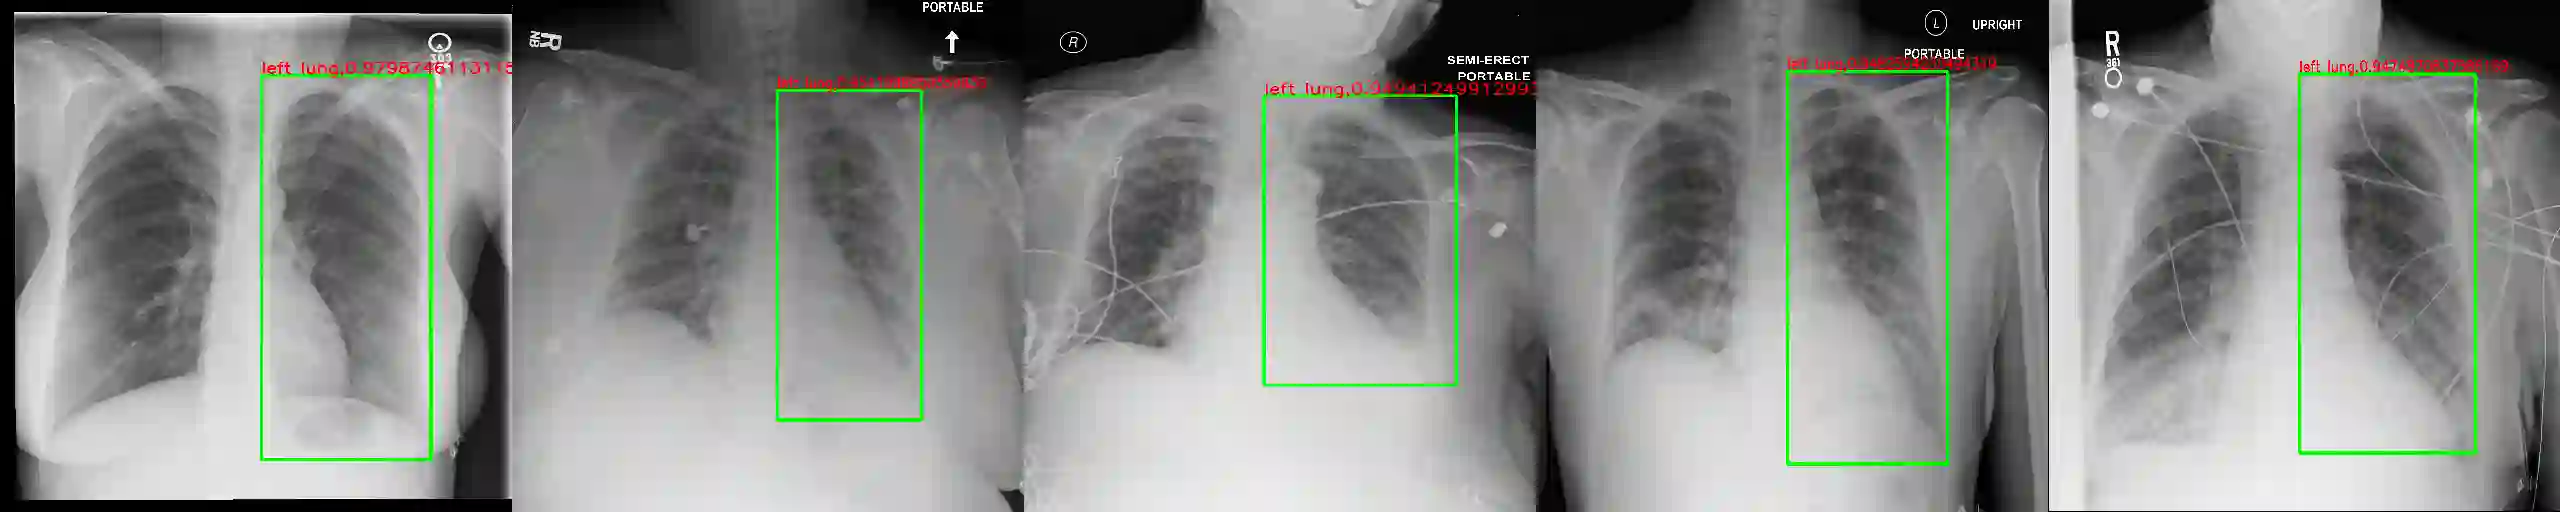

We introduce a novel Region-based contrastive pretraining for Medical Image Retrieval (RegionMIR) that demonstrates the feasibility of medical image retrieval with similar anatomical regions. RegionMIR addresses two major challenges for medical image retrieval i) standardization of clinically relevant searching criteria (e.g., anatomical, pathology-based), and ii) localization of anatomical area of interests that are semantically meaningful. In this work, we propose an ROI image retrieval image network that retrieves images with similar anatomy by extracting anatomical features (via bounding boxes) and evaluate similarity between pairwise anatomy-categorized features between the query and the database of images using contrastive learning. ROI queries are encoded using a contrastive-pretrained encoder that was fine-tuned for anatomy classification, which generates an anatomical-specific latent space for region-correlated image retrieval. During retrieval, we compare the anatomically encoded query to find similar features within a feature database generated from training samples, and retrieve images with similar regions from training samples. We evaluate our approach on both anatomy classification and image retrieval tasks using the Chest ImaGenome Dataset. Our proposed strategy yields an improvement over state-of-the-art pretraining and co-training strategies, from 92.24 to 94.12 (2.03%) classification accuracy in anatomies. We qualitatively evaluate the image retrieval performance demonstrating generalizability across multiple anatomies with different morphology.